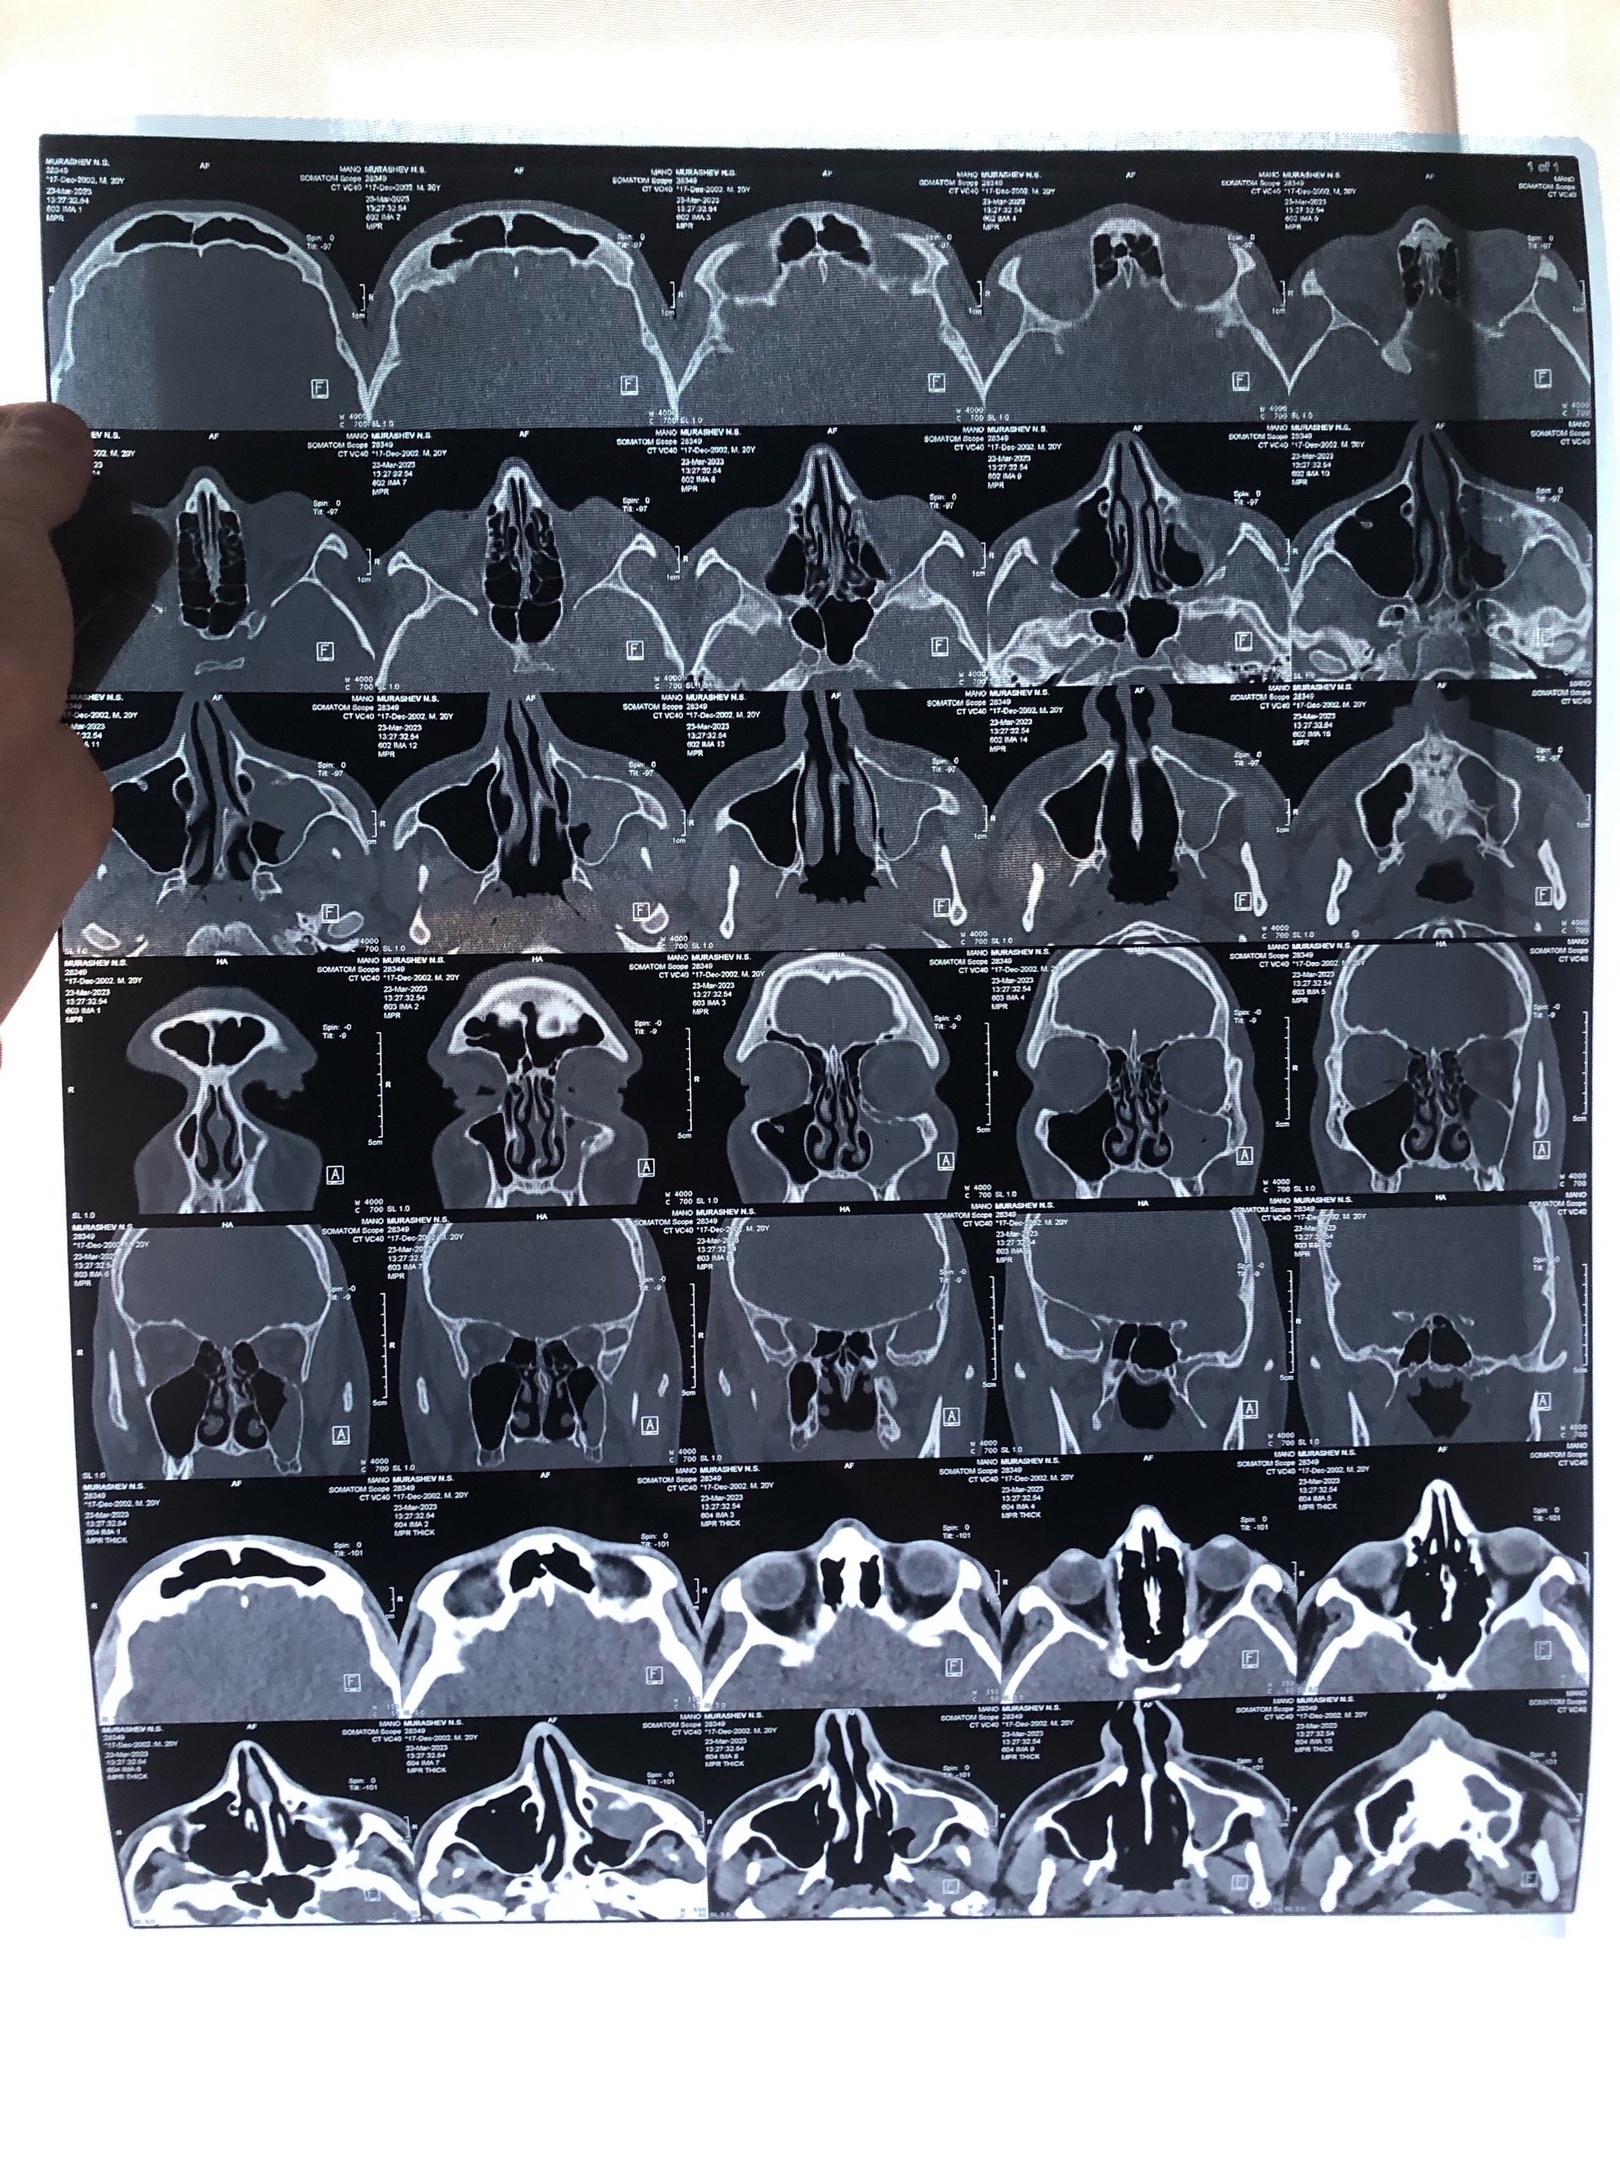

Здравствуйте, поставили диагноз Хронический риносинусит (полипы, кисты ВЧП слева), деформация перегородки носа с затруднением носового дыхания.

Основываясь на МСКТ носовых пазух и заключению по ниму от другого врача, а именно "Субтотальное снижение воздушности левой верхнечелюстной пазухи (кисты или полипы). Искривление носовой перегородки, с носовой шпорой", а так же моим показаниям.

Так же прикрепляю МСКТ.

МСКТ